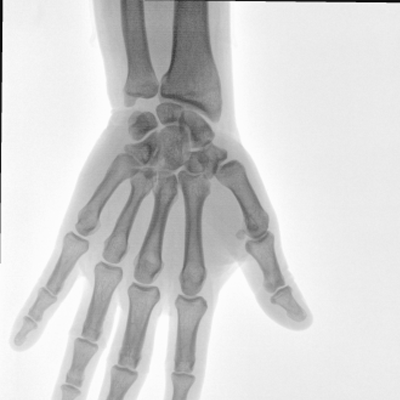

大尺寸動(dòng)態(tài)平板探測(cè)器,高DQE、低噪聲、圖像清晰。采用多分辨率圖像增強(qiáng)處理技術(shù),不同部位不同圖像處理算法,滿足客戶多樣化的需求。

臨床適用科室:骨科、普通外科、矯形外科、創(chuàng)傷外科、泌尿外科、脊柱外科、疼痛外科、消化科、婦科等科室。